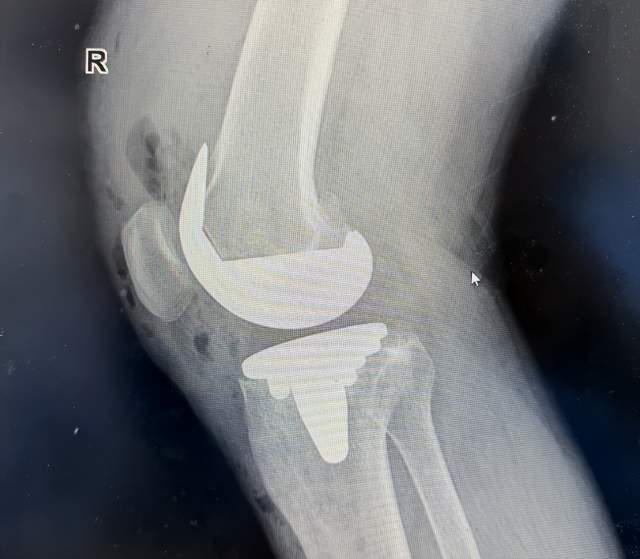

术后次日,张大叔在助行器辅助下站立活动时激动地表示:“走路不疼的感觉真好!”骨科康复治疗师陈志梦介绍,生物型置换因无需等待骨水泥固化,术后康复速度提升30%左右,这对老年患者尤为关键。

康复密码:因无需骨水泥凝固等待期,患者通常术后6小时即可开始踝泵运动,48小时内下地,住院时间缩短至3-5天。

术后影像